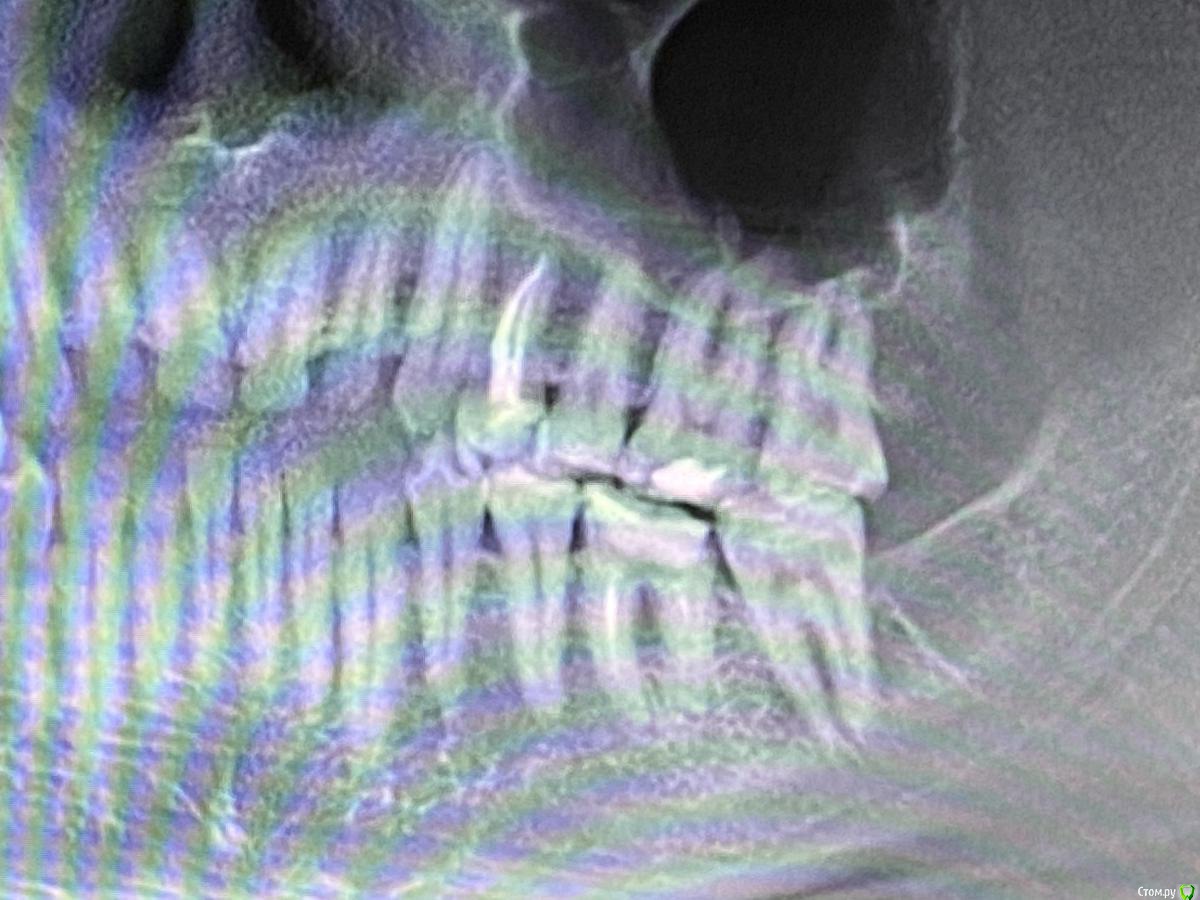

Пациент007 Опубликовано 4 апреля, 2020 Поделиться Опубликовано 4 апреля, 2020 Всем здравствуйте! Зуб когда-то пролеченный резорцин-формалиновым методом. Уже почти весь рассыпался. Но никак не беспокоит. Предложили два варианта: удаление и имплантация. Или перелечить, поставить вкладку и коронку, но никаких гарантий дать не смогут. Прошу оценить ситуацию. Ссылка на комментарий

Пациент007 Опубликовано 4 апреля, 2020 Автор Поделиться Опубликовано 4 апреля, 2020 Снимок Ссылка на комментарий

red_butler Опубликовано 5 апреля, 2020 Поделиться Опубликовано 5 апреля, 2020 Спасибо за ответ. Если можно, аргументируйте, пожалуйстаСтепень разрушения зуба не позволяет его восстановить Ссылка на комментарий